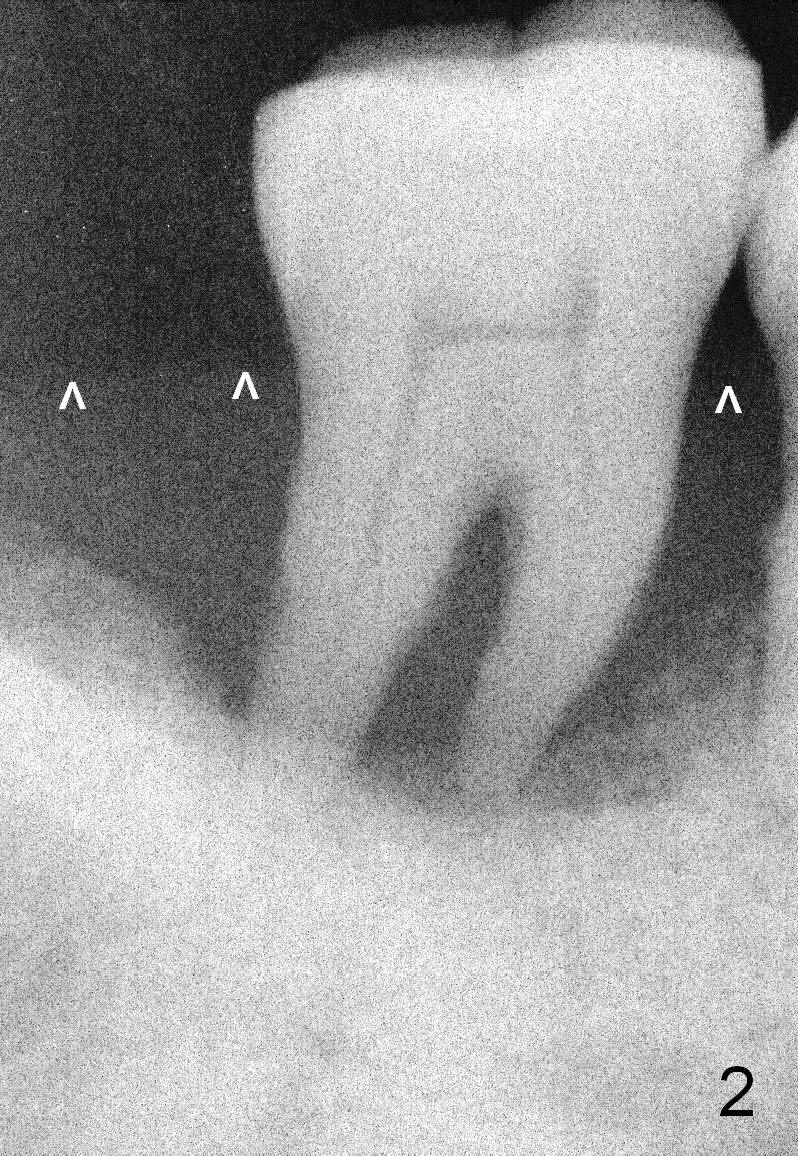

A 46-year-old lady has generalized moderate localized severe (Fig.1 (panorex) #31) chronic periodontitis.  Surprisingly there is sufficient bone height (Fig.1 white dashed line: upper border of the Inferior Alveolar Canal).  The gingiva is quite thick (Fig.2 (PA) arrowheads: gingival margin).  In order to prevent thread exposure associated with immediate implant, a bone-level implant will be placed (Fig.3 5.3x8 mm; green lines) with a long abutment (5.8x5.5 mm (black lines) (6 mm cuff; red lines)).   Initial osteotomy depth is between 14 and 17 mm.  Insert a parallel pin and take the 1st intraop PA.  Use reamers to enlarge osteotomy and collect autogenous bone.  A drill with a stopper (5x8mm) will be used prior to placement of the implant mentioned above.  Since the opposing is a removable partial denture, an immediate provisional at the site of #31 should be safe to be fabricated.  Bone graft will be placed to cover the exposed implant surface.  The remaining gap will be filled with collagen dressing and the provisional.  A temporary abutment is the other option.  The shoulder of the temporary abutment will be subgingival to long extent.  Is the plan well executed?